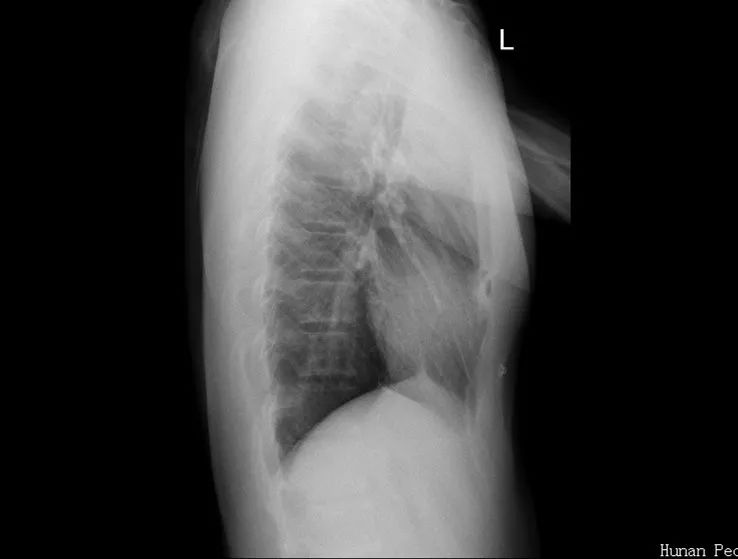

術(shù)前X片可以看到體內(nèi)的矯形鋼板。

取出鋼板后,凹陷畸形完全矯正。

7月9日上午,手術(shù)只花了不到1小時(shí)便順利完成,據(jù)了解,這是省內(nèi)醫(yī)院首次將漏斗胸鋼板取出手術(shù)納入日間手術(shù)病種范疇。第二天上午,小銘進(jìn)行術(shù)后X光復(fù)查,顯示畸形完全矯正,手術(shù)效果良好,下午就辦理了出院手續(xù)。